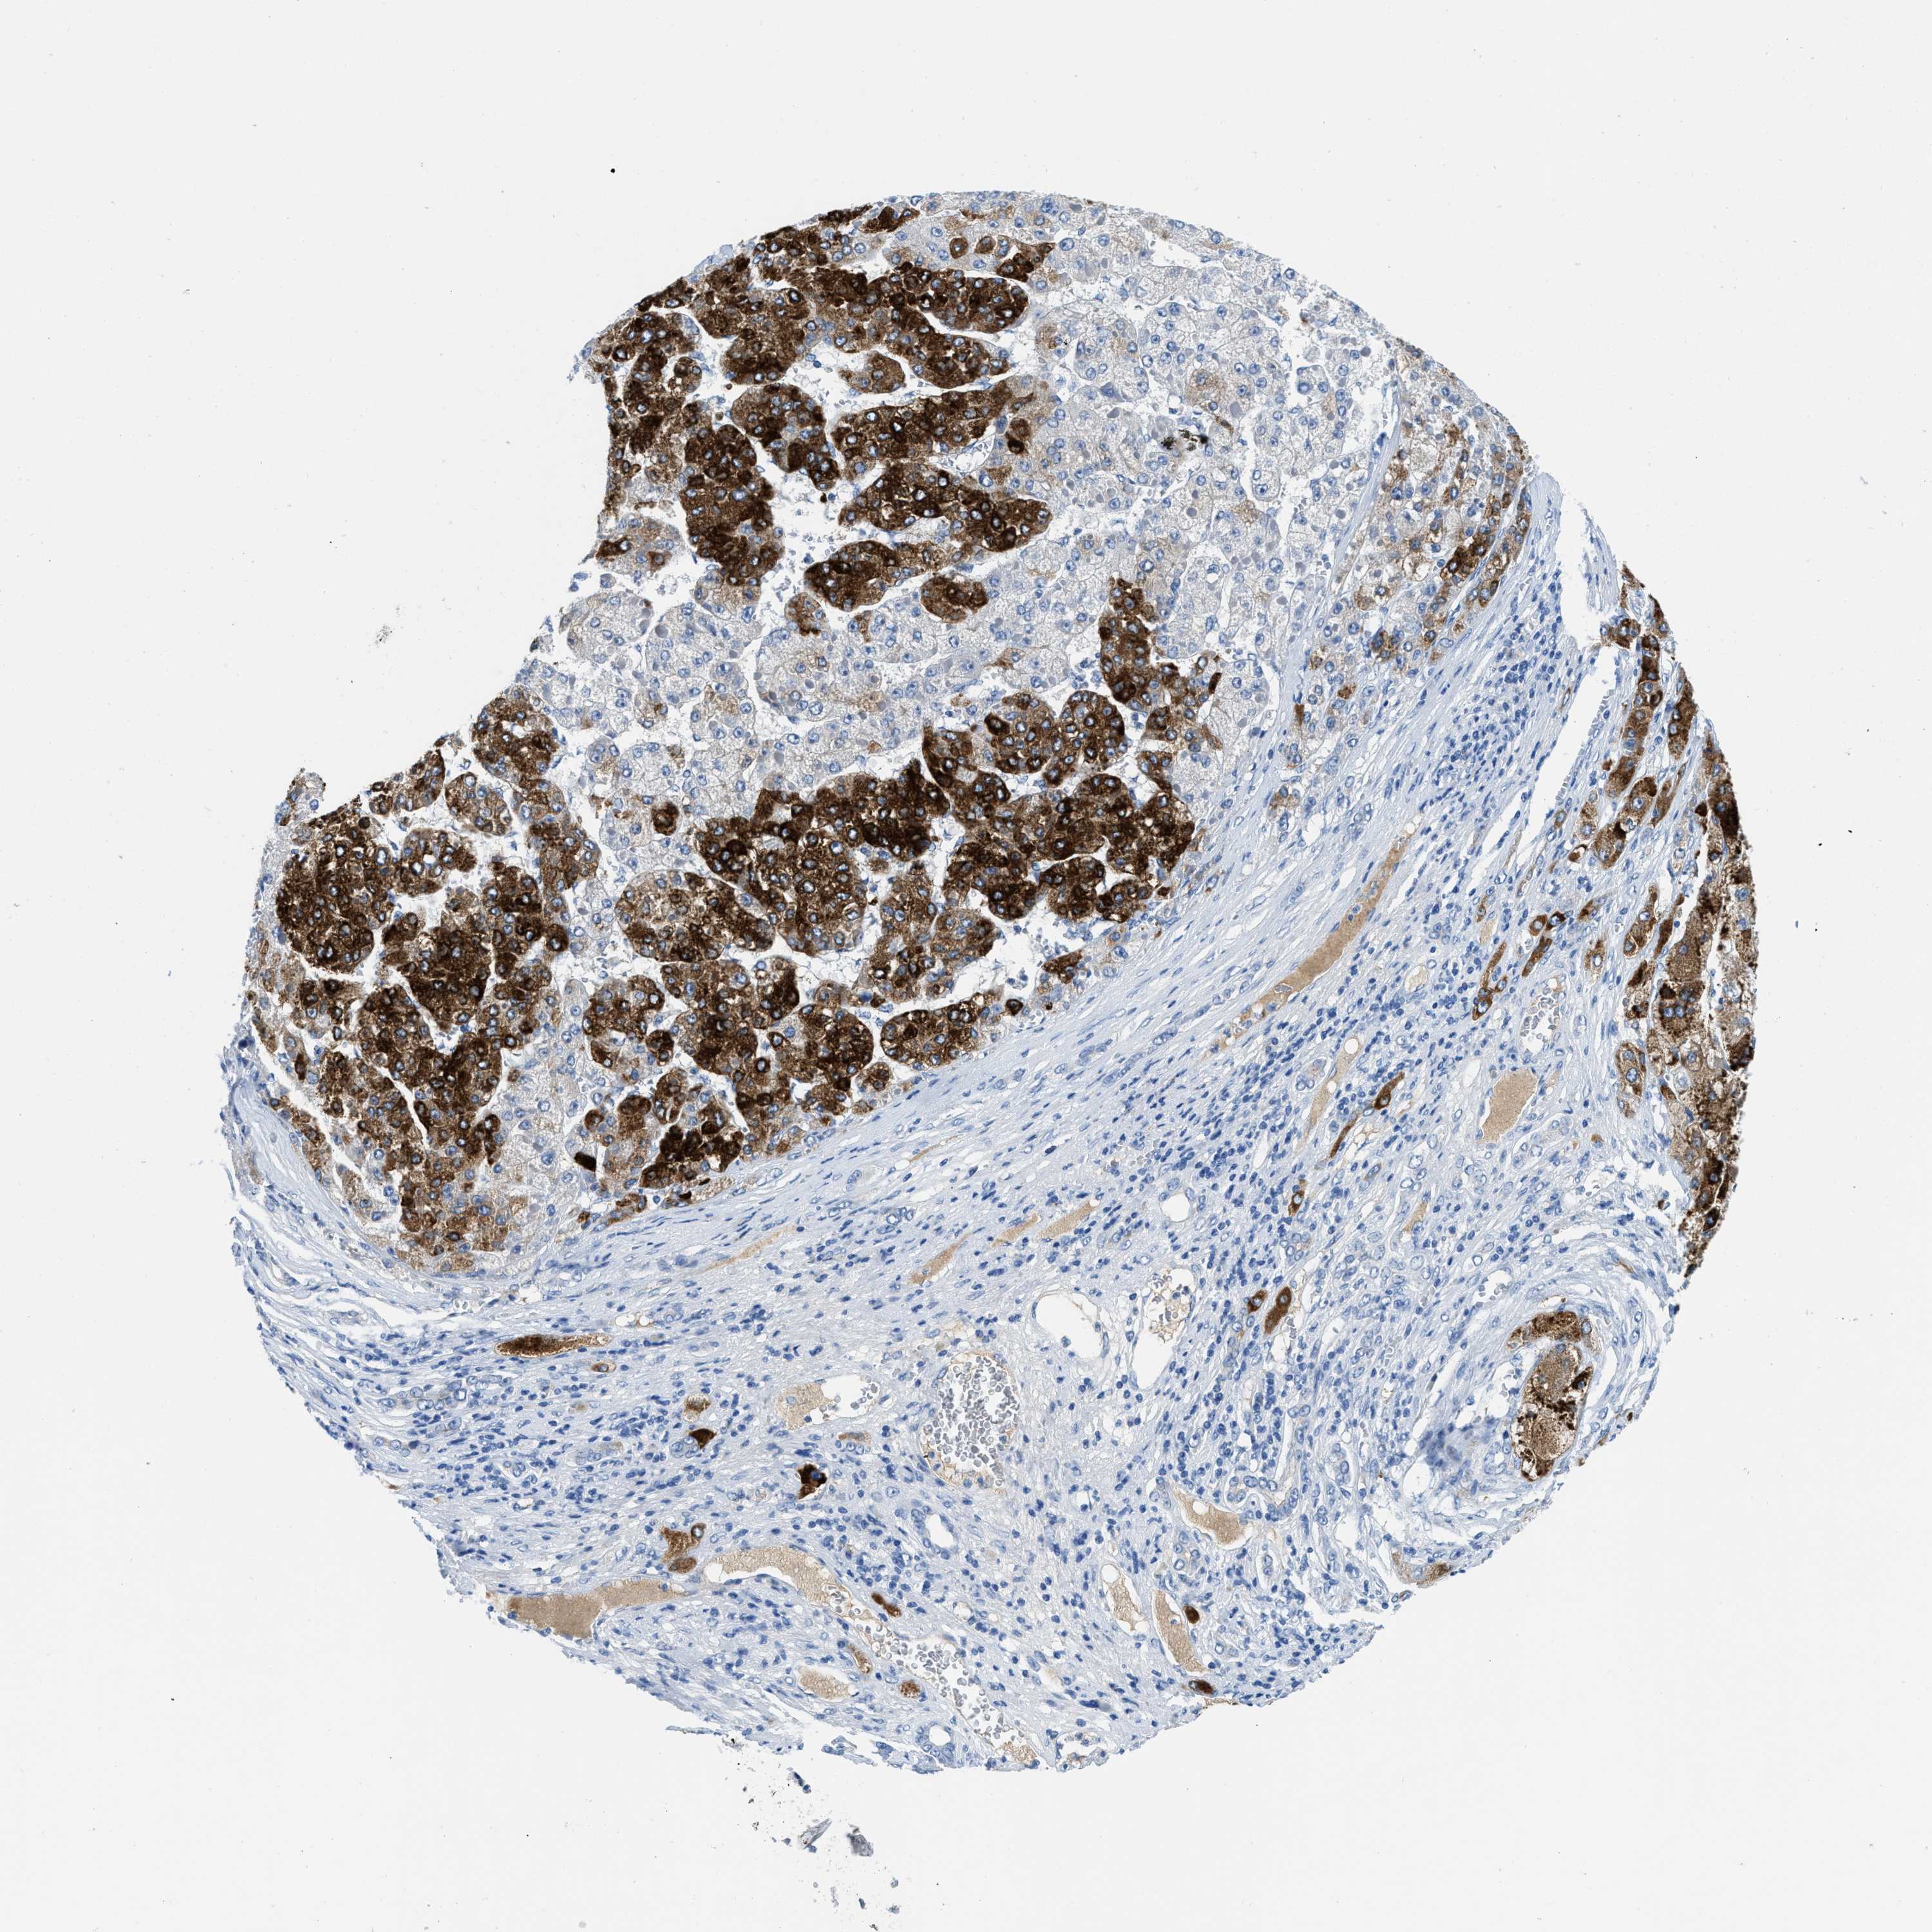

LIVER CANCER - Protein expressioni

A mouse-over function shows sample information and annotation data. Click on an image to view it in a full screen mode. Samples can be filtered based on level of antibody staining by selecting one or several of the following categories: high, medium, low and not detected. The assay and annotation is described here.

Antibody stainingi

Antibody staining in the annotated cell types in the current human tissue is reported as not detected, low, medium, or high, based on conventional immunohistochemistry profiling in selected tissues. This score is based on the combination of the staining intensity and fraction of stained cells.

Each image is clickable and will lead to virtual microscopy that enables deeper exploration of all samples and also displays staining intensity scores, fraction scores and subcellular localization as well as patient and tissue information for each sample.

Antibody HPA002027

Antibody CAB016782

Staining

High

Medium

Low

Not detected

Intensity

Strong

Moderate

Weak

Negative

Quantity

>75%

75%-25%

<25%

None

Location

Nuclear

Cytoplasmic/membranous

Cytoplasmic/membranous,nuclear

Carcinoma, Hepatocellular, NOS

Cholangiocarcinoma